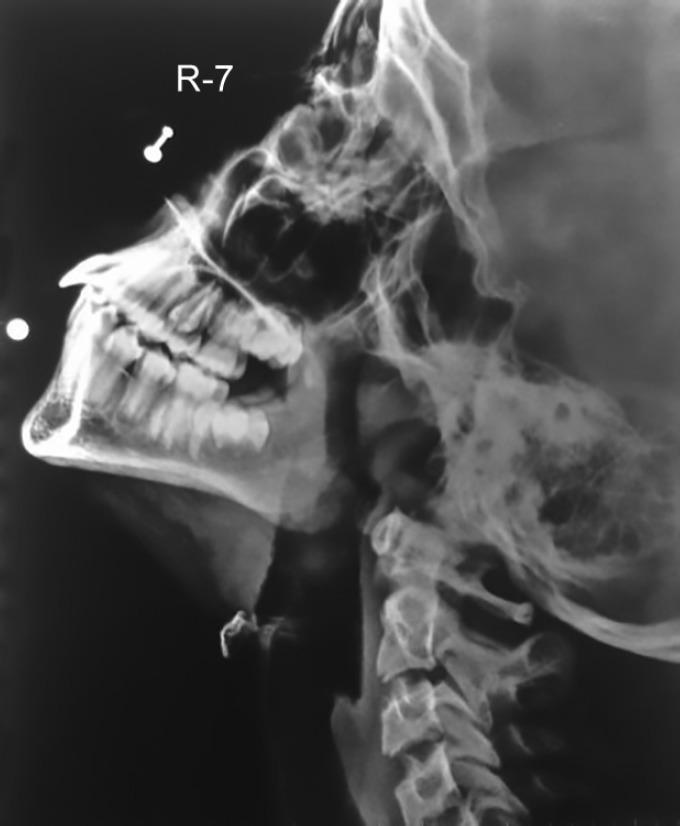

Here we present a rare case of an 8-year-old girl who presented to the department of Pediatric Dentistry with the chief complaint of recurrent painless swelling of the lower lip. This rare presentation of lower lip swelling has not been cited in the oral manifestation of Kawasaki disease before.

我们在此呈现一例罕见病例,一名8岁女孩因下唇反复无痛肿胀为主诉就诊于儿童牙科。这种罕见的下唇肿胀表现此前在川崎病的口腔表现中未被提及。